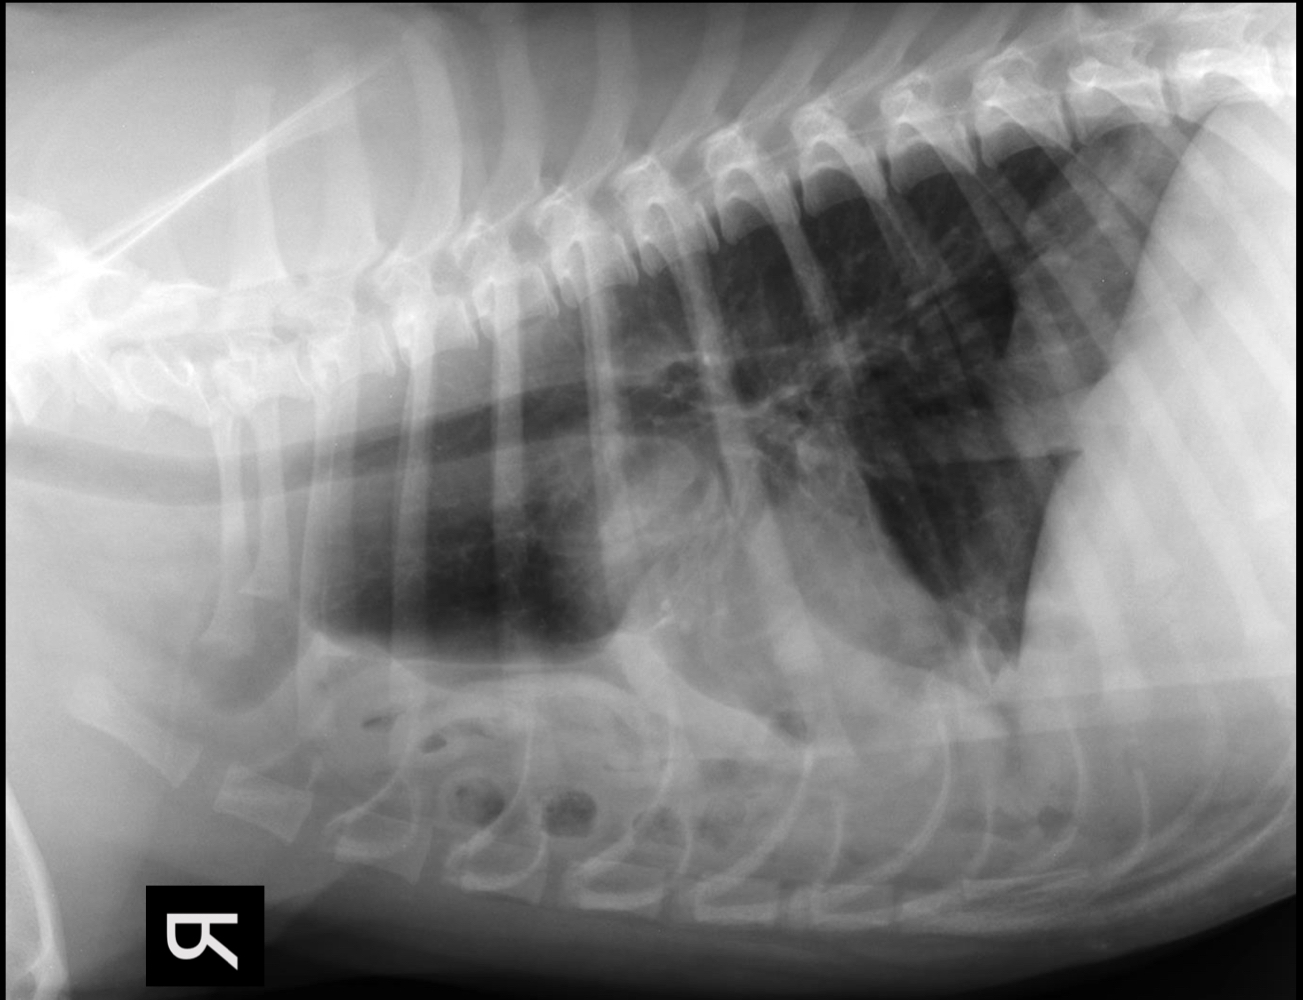

Q

What is seen on this radiograph?

A

• malpositioned stomach with gas within gastric wall (pneumatosis gastri)

• also gas within portal vasculature

GDV!